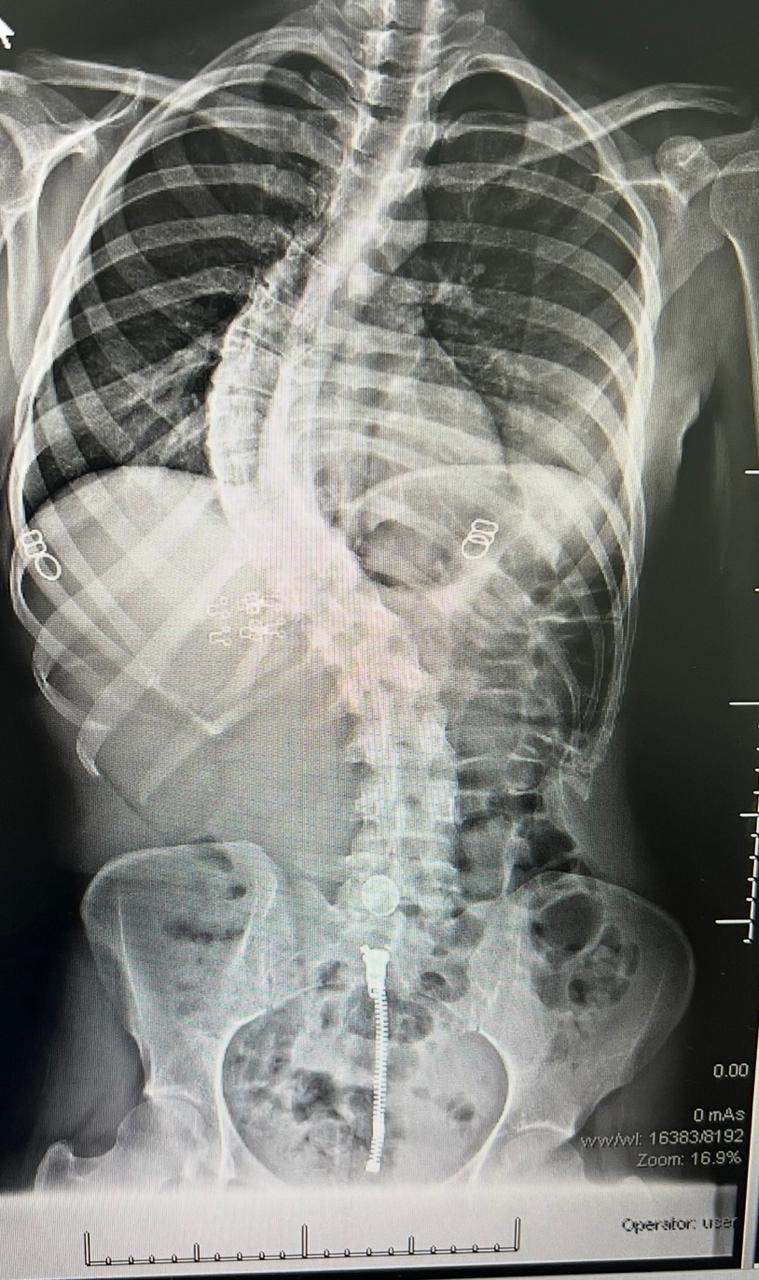

وخضعت الحالتان لتقييم طبي شامل ودقيق تضمن إجراء كافة الفحوصات الإكلينيكية والأشعة المتخصصة، التي كشفت عن وجود تشوهات ودرجات انحناء متقدمة استوجبت التدخل الجراحي العاجل لتفادي المضاعفات.

واستعان الفريق الطبي بأحدث التقنيات العالمية في هذا المجال، معتمداً بشكل أساسي على أجهزة المراقبة العصبية الدقيقة لضمان أعلى معايير الأمان وسلامة الأعصاب الحساسة أثناء إجراء التعديل.

واستغرقت كل عملية نحو ثماني ساعات متواصلة من العمل الدقيق، نظراً لتعقيد الحالات وحاجتها لتنسيق عالٍ ولحظي بين جراحي العمود الفقري وفريق التخدير لضمان استقرار المريض.